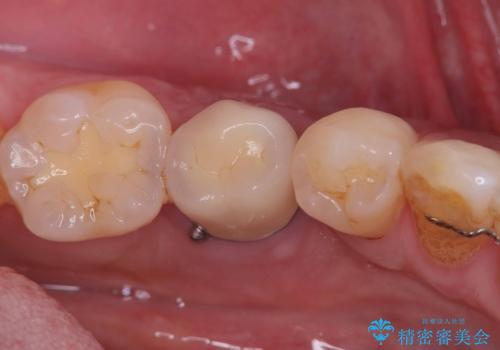

- 20年振りの来院で下顎左右5番にインプラント入れていた患者様です。

右下5番のインプラントは問題ありませんでしたが、左下5番のインプラントがインストール周囲炎に罹患している状態でした。